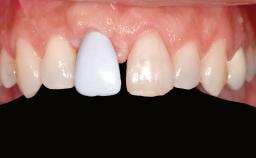

Prosthesis Type FDP

Defining Characteristics One missing tooth to be replaced by an implant-borne crown